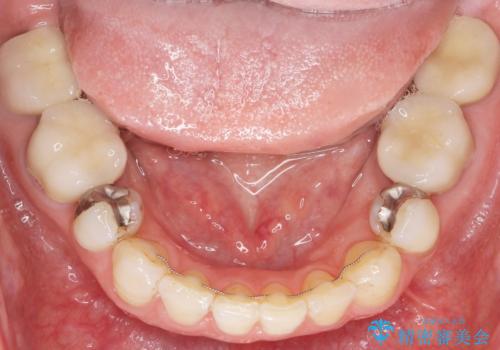

銀歯がなくなったとことで口元の印象が明るくなり、ご満足頂けました。

「これで大きく口を開けて笑っても大丈夫だわ!」と喜んで下さいました。

右上小臼歯(右上5):オールセラミッククラウン エコノミー

下顎両側臼歯(下顎両側67):メタルボンドクラウン エコノミー